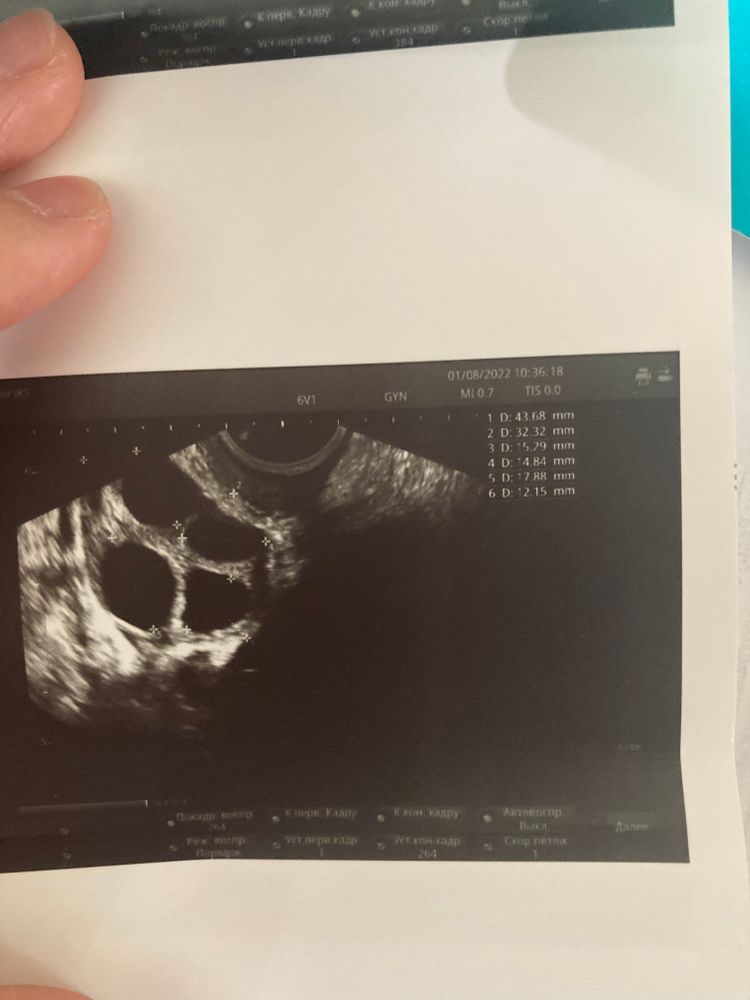

Сегодня 11 день цикла сходила на узи чтобы посмотреть как там яйчники мои и есть ли уже доминантный.

И вот тут пепец🥺😂 В левый яичник-4 Больших фолликул это уже Доминантный?

И в правый яичник-3 фолликул тоже большие …

У вас легкая гиперстимуляция яичников. ответили все фолликулы , доминанты нет. А вот эндометрий подкачал, Он должен быть 8-10 мм. Без укола ХГ 10.000 они не лопнут. А с 16 дня начинайте принимать Утрожестан, он будет способствовать росту эндометрия нормальной 2 фазы цикла